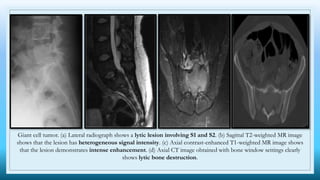

Giant cell tumor. (a) Lateral radiograph shows a lytic lesion involving S1 and S2. (b) Sagittal T2-weighted MR image

shows that the lesion has heterogeneous signal intensity. (c) Axial contrast-enhanced T1-weighted MR image shows

that the lesion demonstrates intense enhancement. (d) Axial CT image obtained with bone window settings clearly

shows lytic bone destruction.